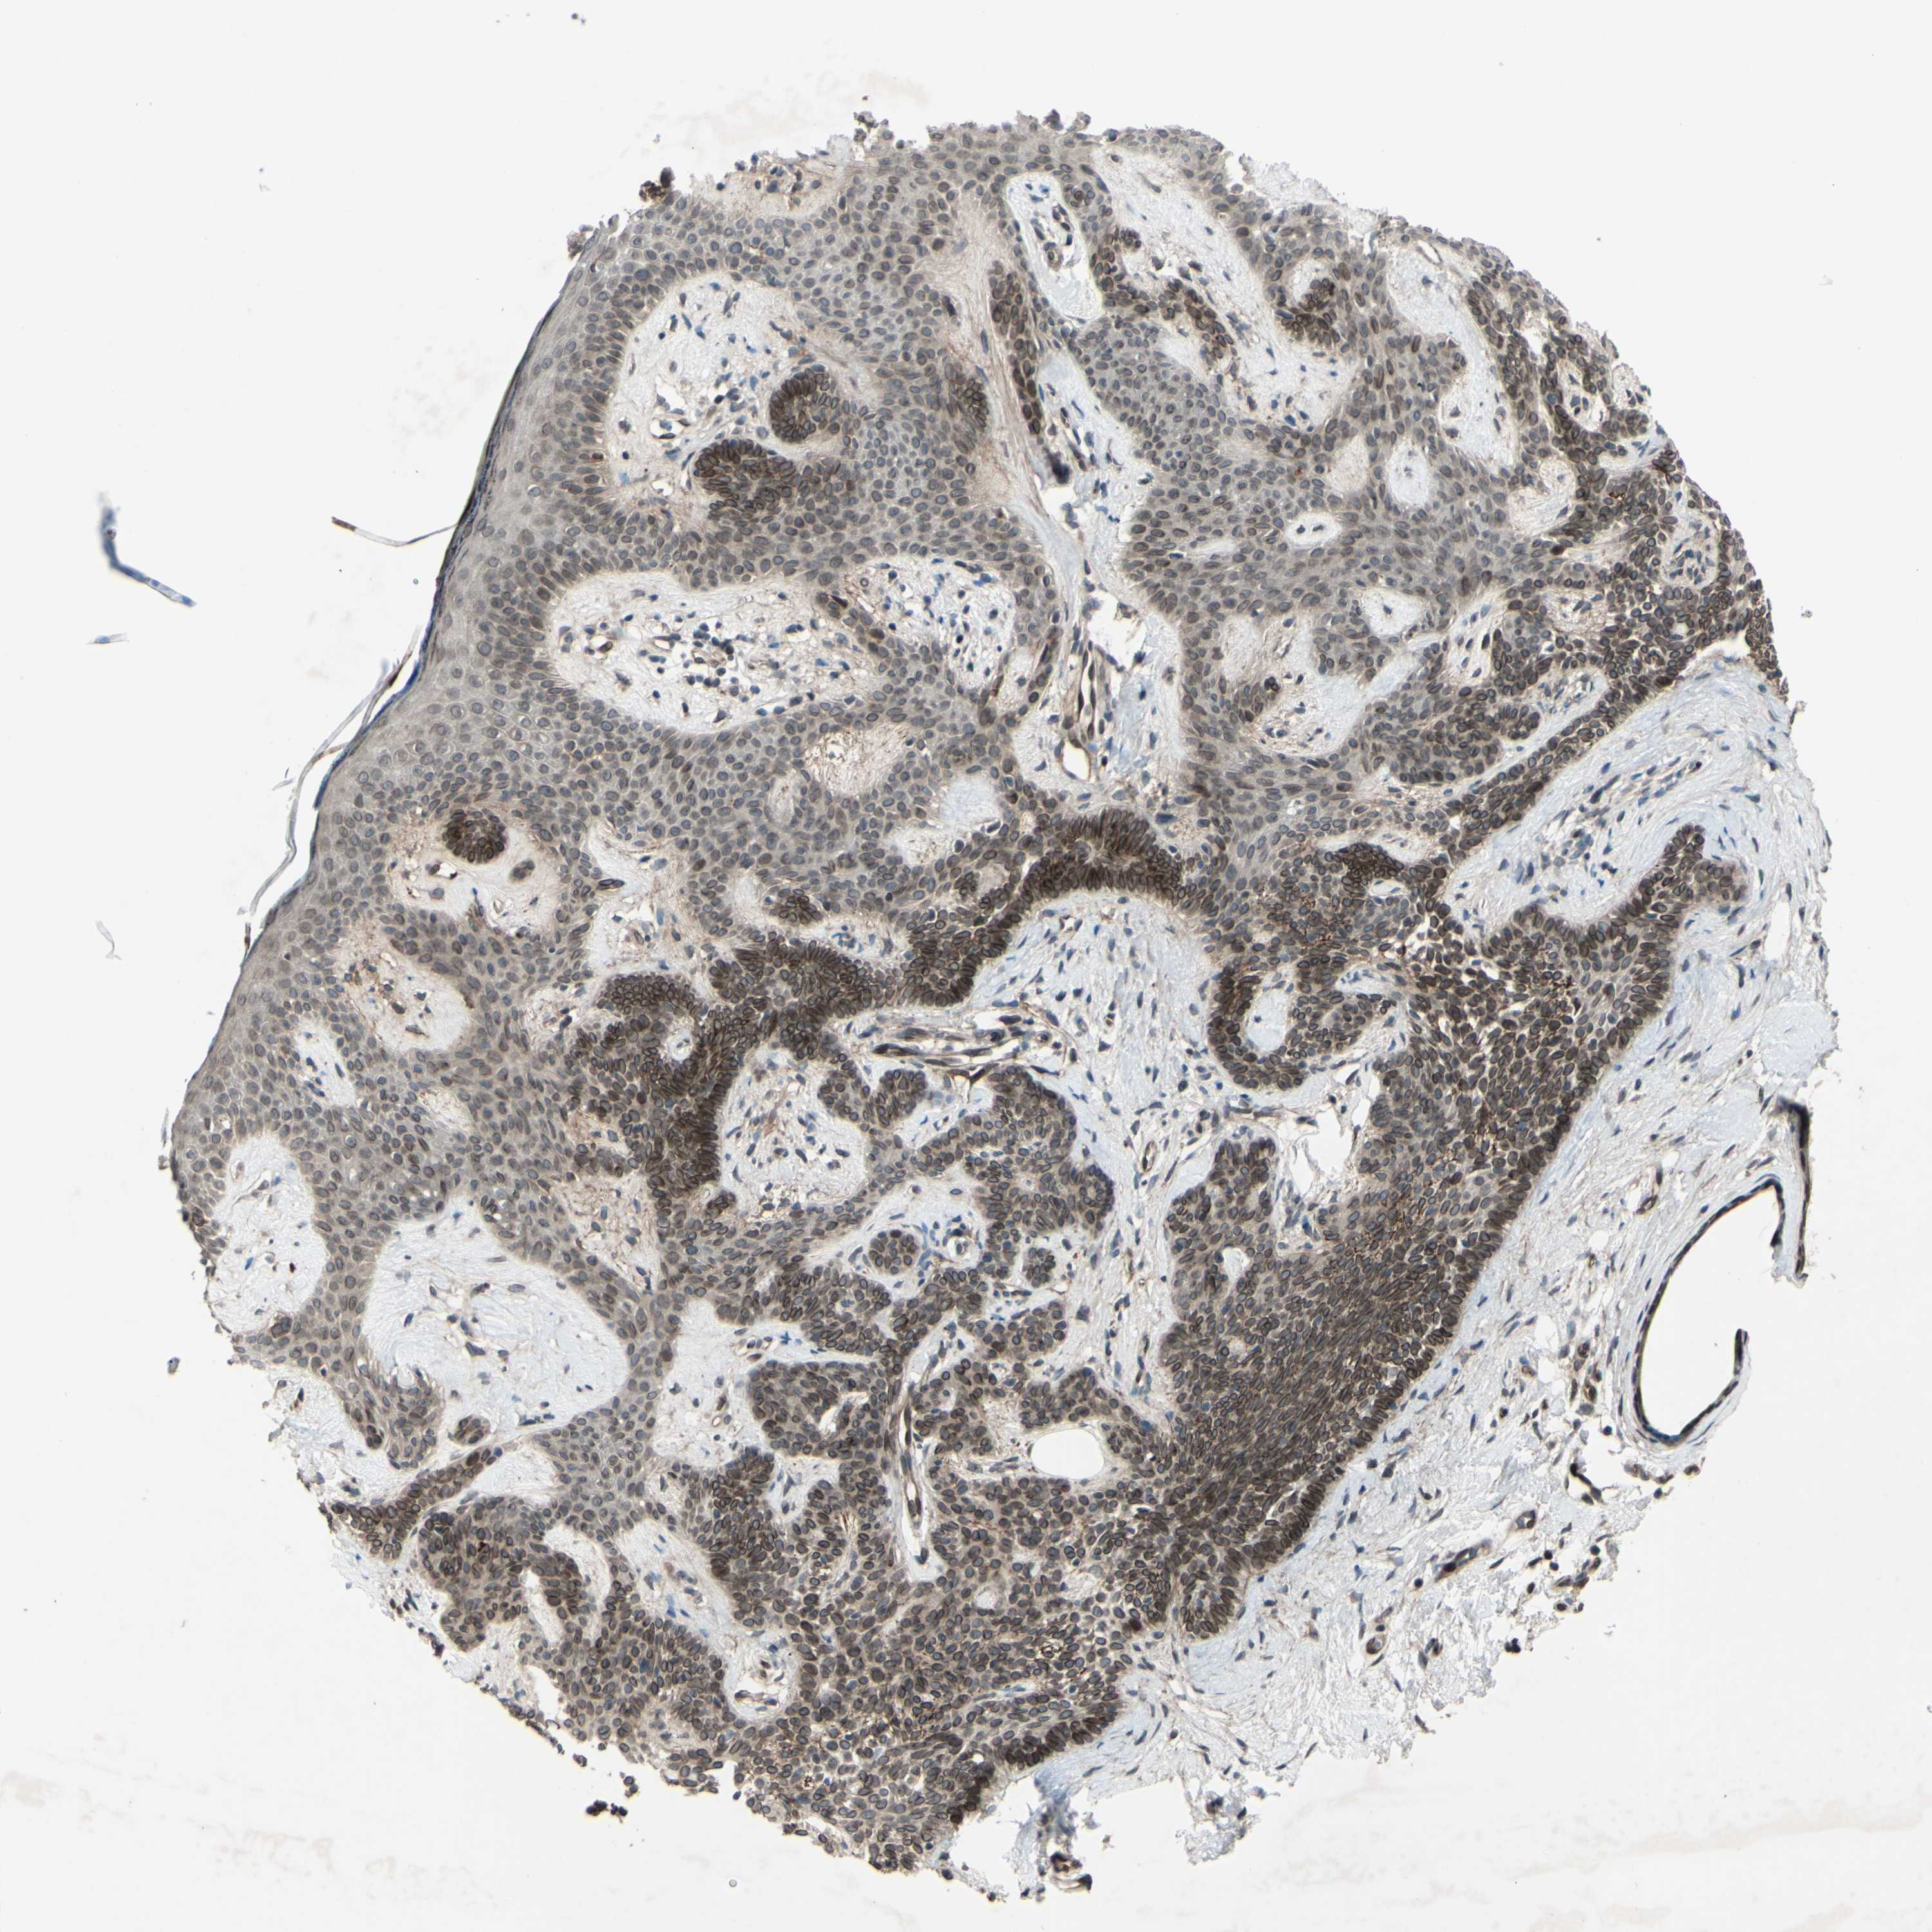

CANCER SKIN CANCER Show tissue menu

Basal cell and squamous cell cancer

SKIN CANCER - Protein expressioni

A mouse-over function shows sample information and annotation data. Click on an image to view it in a full screen mode. Samples can be filtered based on level of antibody staining by selecting one or several of the following categories: high, medium, low and not detected. The assay and annotation is described here.

Each image is clickable and will lead to virtual microscopy that enables deeper exploration of all samples and also displays staining intensity scores, fraction scores and subcellular localization as well as patient and tissue information for each sample.

Antibody HPA010811

Staining

High

Intensity

Strong

Quantity

>75%

Location

Nuclear

Squamous cell carcinoma, NOS